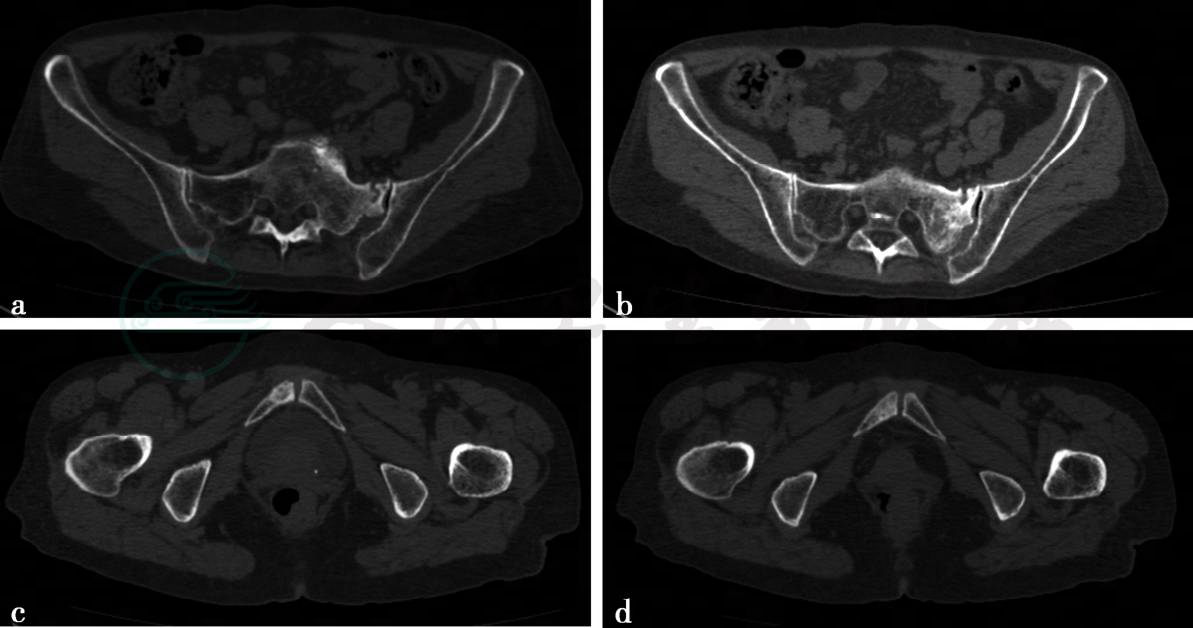

病例3,75岁,女性,腰骶部及臀部疼痛,有肺癌病史。

病例5-1-3:CT平扫。

图1 图1a~d,骨盆CT平扫(骨窗),骶骨左侧可见骨折线,周围伴有反应性改变。右侧耻骨下支密度不均匀升高

病例3,功能不全骨折。